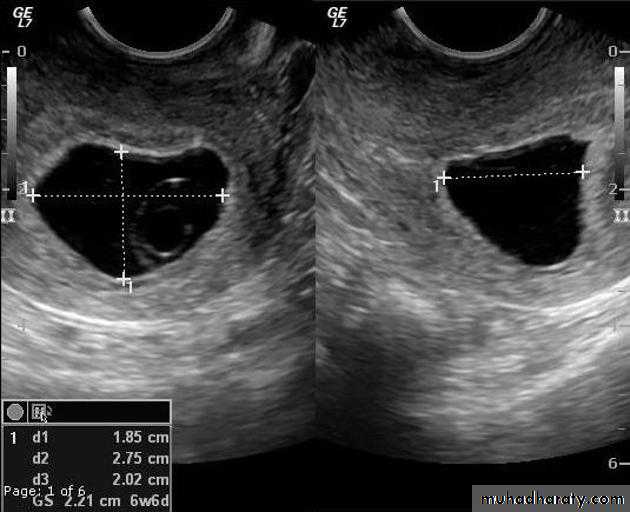

Blighted ovum

Anembryonic pregnancy is a form of a failed early pregnancy, where a gestational sac develops, but the embryo does not form. The term blighted ovum is synonymous with this, but is falling out of favour and is best avoided.Radiographic features

Ultrasound

An anembryonic pregnancy may be diagnosed when there is no fetal pole identified on endovaginal scanning , and:the size of the gestational sac is such that a fetal pole should be seen: MSD ≥25 mm on TVS (by RCOG criteria)